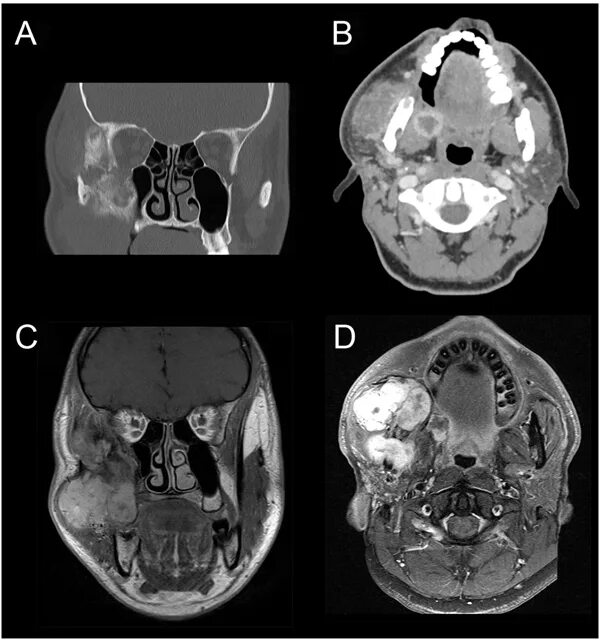

Фиброма кт